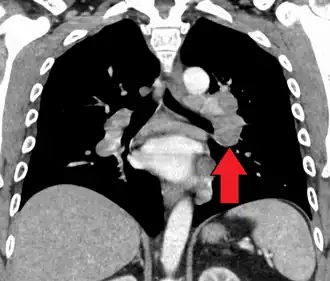

-

Hilar adenopathy especially on the person's left (AP CXR) -

Hilar adenopathy especially on the person's left (lateral CXR) -

Hilar adenopathy especially on the person's left (coronal CT) -

Hilar adenopathy especially on the person's left (transverse CT)